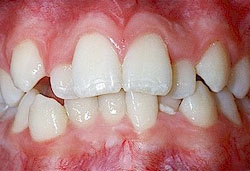

- *Răng mọc chen chúc:

- Răng mọc chen chúc là tình trạng các răng sắp xếp lộn xộn, không ngay ngắn trên cung hàm , răng mọc không đều, các răng khấp khểnh do thiếu chỗ (răng quá to hay xương hàm cung răng quá nhỏ không đủ chỗ để các răng sắp xếp).